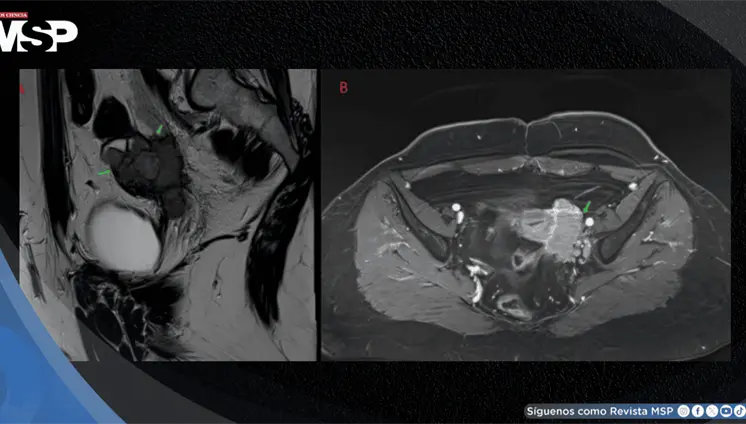

Lo que comenzó como un cuadro frecuente de dolor pélvico y dismenorrea en una mujer, terminó siendo un carcinoma folicular originado en estruma ovárico maligno. La paciente tenía solo 35 años, marcadores tumorales completamente normales y ninguna alteración tiroidea.

A pesar de los análisis normales, presentaba reserva ovárica baja y hallazgos ecográficos anormales. Durante la cirugía se descubrió daño severo en sus órganos reproductivos, con adherencias, trompas bloqueadas y destrucción del tejido ovárico.